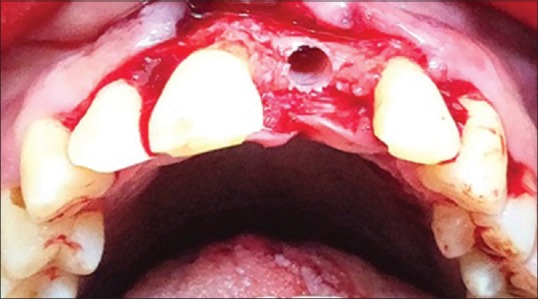

For Group II, [Figure 1a and 1b] Osteotomy was prepared to the desired depth using the pilot drill (clockwise drill speed 800–1500 rpm with copious irrigation) thereafter Osseodensification drills were used in sequence as per the implant diameter protocol).[7] For example, if a 3.75-mm implant was to be placed, drilling is performed in a clockwise direction.

Figure 1.

(a) DENSAH KIT. (b) Preoperative frontal view

Using VT1525, then depending on the density of the bone (soft or medium), the drill motor is reversed (counterclockwise drill speed 800–1500 rpm with copious irrigation). Gradually wider diameter burs were used, i.e., VT1828, VT2535, and VT2838 [Figure 2]. The final placement of implant [Figure 3] was done, and simultaneous buccal veneer grafting was performed.